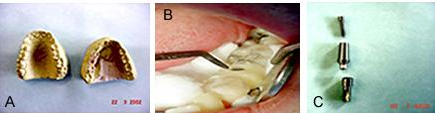

Prótese.

Figuras 8 a, b e c.

Figura 8a. São os modelos de trabalho, superior e inferior, para acerto de oclusão. No modelo inferior está construído o guia cirúrgico, que terá como vimos duas funções.

Primeiro realmente como guia na cirurgia e em seguida como transferente do implante para o modelo de trabalho, assim, o modelo de estudo e confecção de guia, servirá também, como veremos de modelo de trabalho para a confecção da coroa a ser colocada, sobre o implante.

Figura 8b. São as peças que compõem os “abutmans” do sistema Conect a ser usados para confecção da coroa.

Figura 8c. Mostra o guia cirúrgico colocado na posição, para fixação do monta implante, que foi recolocado como mostramos na figura 8a e b ao guia, para servir de transferente para o modelo de trabalho. Essa fixação, deve ser cuidadosa, usando-se para isto resina de autopolimerização, pois o parafuso de fixação não deve ser envolvido de resina, caso contrário a peça não poderia ser mais removida.